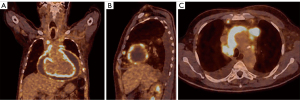

Repeated chest MSCT confirmed the presence of a circumferential pericardial effusion, but also revealed irregular growths at the pericardium with significant imbibition, suggesting the potential for pericardial mesothelioma (Figure 4A,4B). Another pericardiocentesis was conducted, resulting in the removal of 3,000 mL of hemorrhagic fluid.

Color Doppler imaging indicated thrombosis in the subclavian, axillary, and brachial veins, along with the left internal jugular vein. An intensely fluorodeoxyglucose (FDG)-avid mass and significant imbibition in a visceral area of the pericardium were observed on an FDG positron emission tomography (PET) scan, with a maximum standard uptake value (SUV) of 11.2. Additional smaller FDG-avid masses and intense imbibition were noted at the interlobar and costal pleura and the paratracheal and supracarinal lymph nodes, with a maximum SUV of 8.2 (Figure 5A-5C).